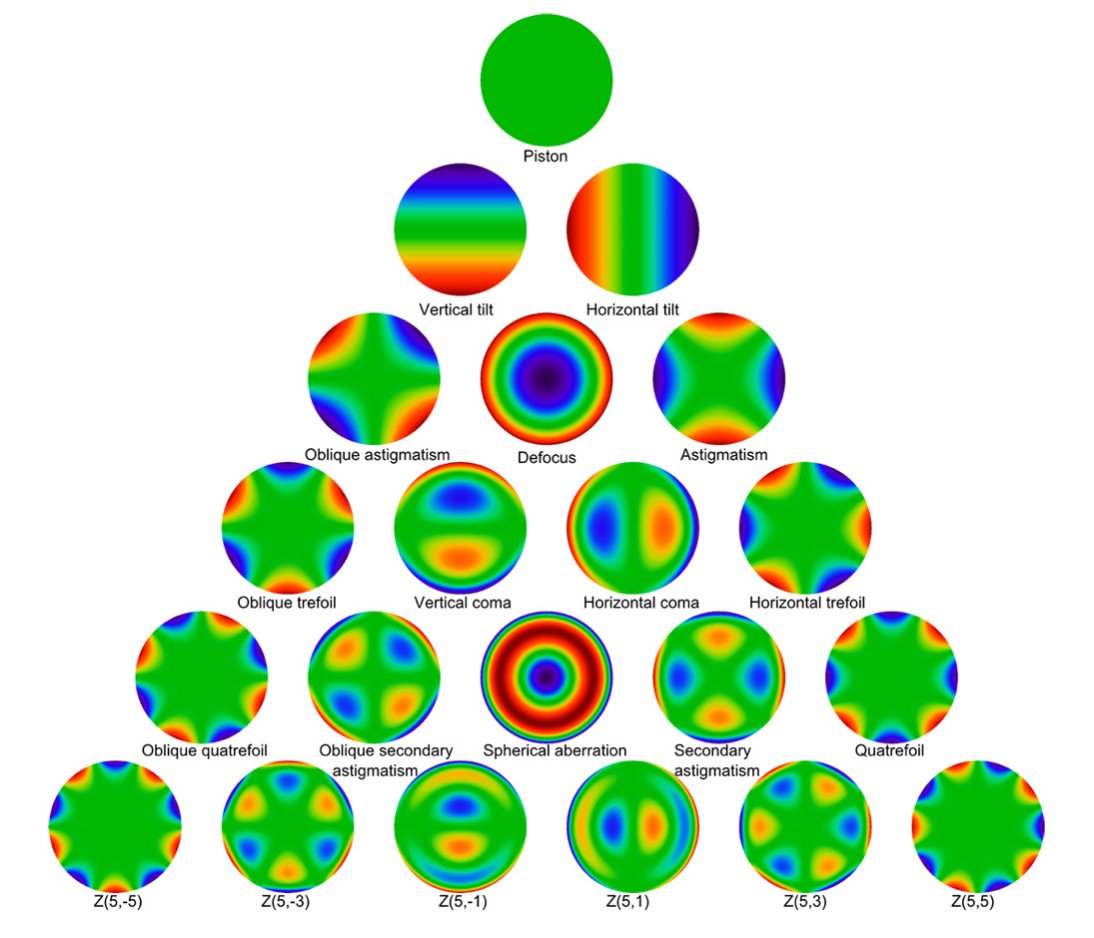

Aberrometría Ocular